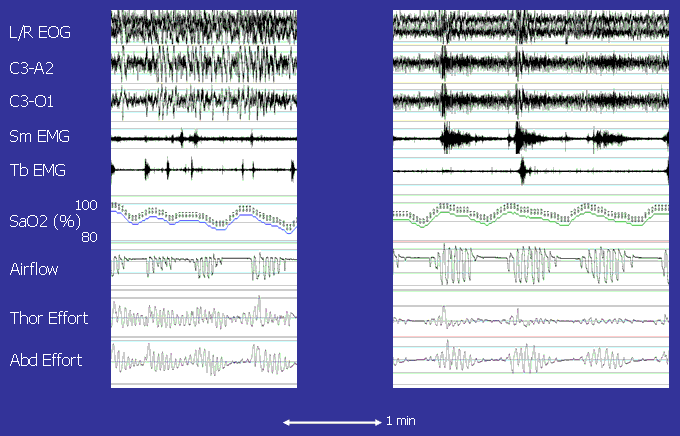

A 69M presented with loud snoring, sleep disruption and daytime sleepiness. This slide illustrates two polysomnographic segments from the same night in this patient. How would you characterize the sleep disordered breathing patterns in each slide, and how would you account for any differences in these patterns?

The patient had loud snoring, sleep disruption and daytime sleepiness. He also had a history of atrial fibrillation and well compensated heart failure, a moderately dilated left ventricle and evidence for volume overload (peripheral edema) on exam. These recordings demonstrate predominantly obstructive apneas (O) at the start of the night (L panel), and mixed (M) and central (C) apneas at the end of the night (R panel). This shift is associated with a prolongation in circulation time (see red arrows).

The switch to Cheyne Stokes breathing patterns patterns is likely related to the finding that the circulation time lengthened over the course of the night (see Figure). The circulation time (CT) is estimated by measuring the time between apnea termination and the SaO2 nadir. It is determined by the circulating blood volume (Volume) and cardiac output (CO, Volume/time) as described by the following relationship:

The circulation time is normally less than 20 seconds. Increases in central blood volume and/or reductions in cardiac output lead to a prolongation of circulation time. Increases in the circulation time cause feedback delay between the lungs and carotid chemoreceptors. When the circulation time in prolonged, it will take longer for ventilatory disturbances in the lungs to be sensed by the chemoreceptors. This delay leads to over- and undershooting of ventilation, and a periodic breathing pattern of the central or Cheyne-Stokes type.